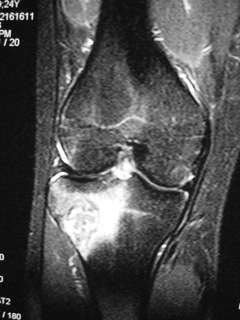

MRI (Fig. 4-7)

• Central low signal intensity with peripheral enhancement on T1-weighted images

• Heterogeneous high signal intensity with low signal in surrounding sclerotic bone on T2-weighted images

Fig. 5

Fig. 4-7: MR imaging of a benign fibrous histiocytoma of the proximal tibia demonstrates a heterogeneous high signal intensity and low signal intensity with surrounding sclerotic bone on T2-weighted images. T1-weighted images show low signal intensity. No soft tissue mass is visible.